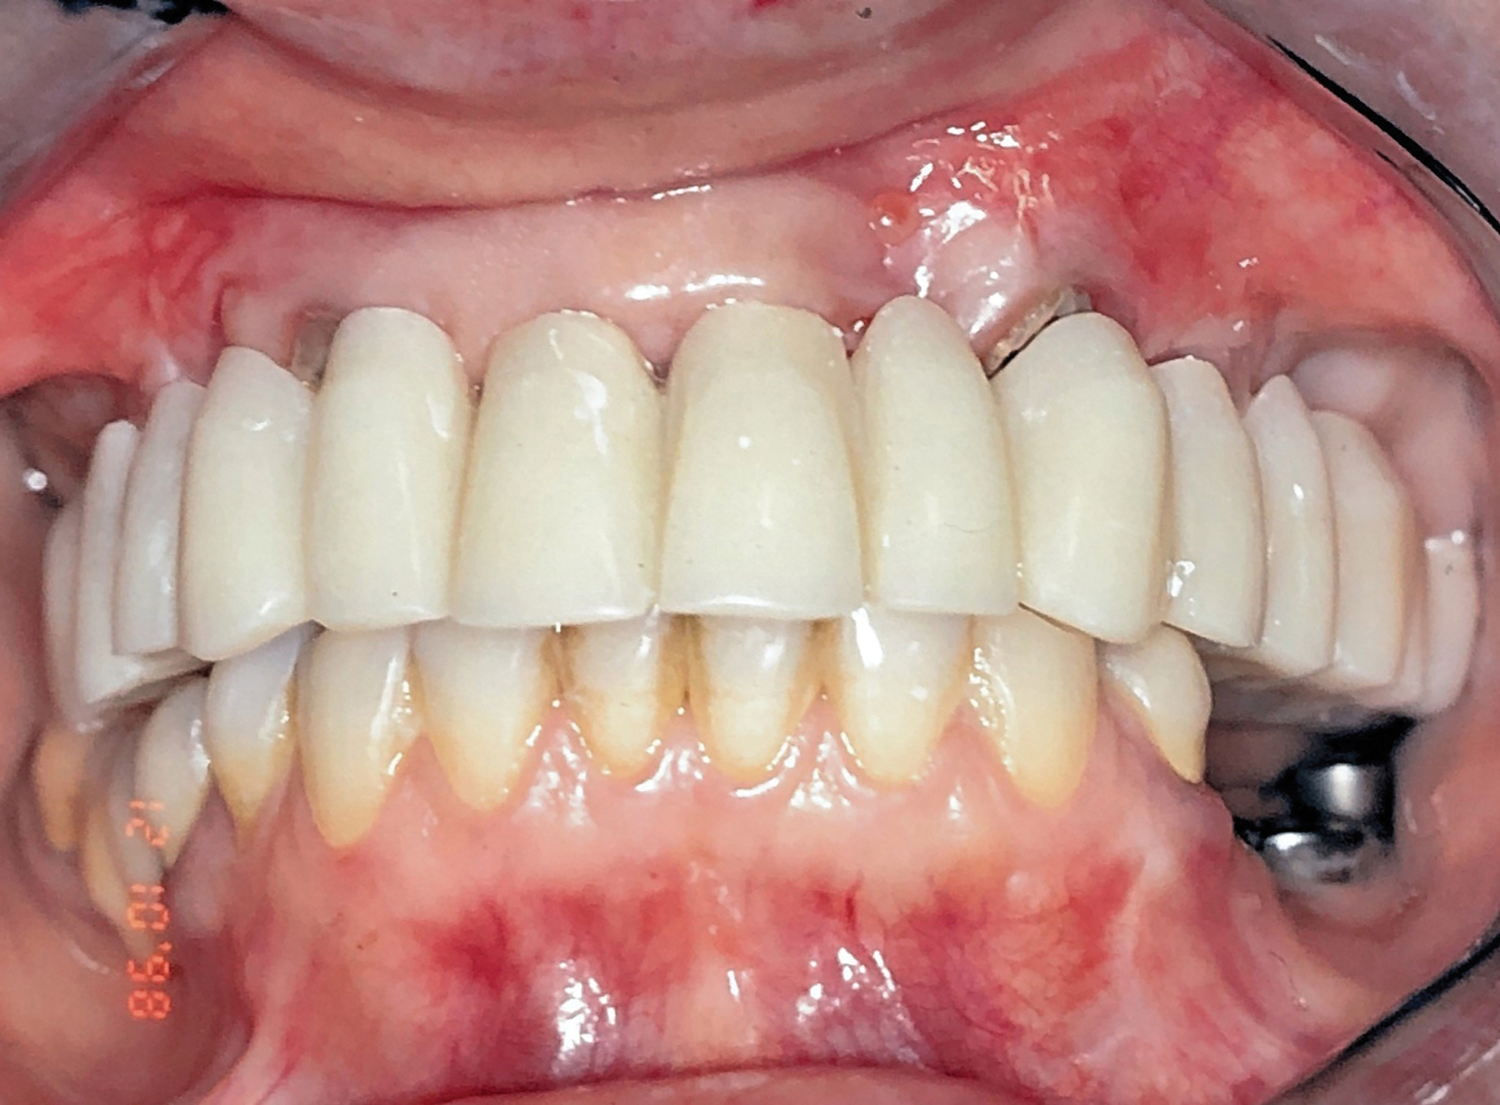

Fig 6. Frontal view after insertion of provisional restoration into the TIs and abutment teeth.

Figure 6

Acrylic resin was then added to the metal bar. The bar was removed to verify a parallel path of insertion and then placed back into the proper position. The maxillary fixed provisional prosthesis was relined with acrylic over the metal bar, abutments, and TIs (Figure 6). The titanium bar was incorporated into the transitional provisional prosthesis. The patient was instructed to close into a previously determined vertical dimension of occlusion until polymerization of the reline material occurred.

The implant-supported, screw-retained, hybrid acrylic complete denture in the maxilla and the mandibular implant fixed prostheses were delivered after torquing the custom abutments to 32 Ncm and the octa abutments to 35 Ncm, and metal frames, including the interlocks, were tried-in. After consensus was obtained on the phonetics, occlusion, and esthetics (Figure 15), the fit was verified by periapical radiographs. The patient, who was very satisfied with the result, was instructed in proper oral hygiene.